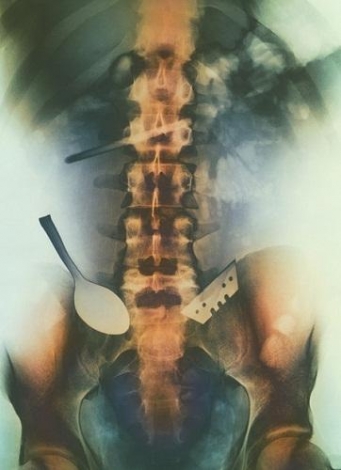

14558096207506654058.jpg

這張彩色X照片展示了病人吞入的物體,其中包括一把勺子和一個刀片。